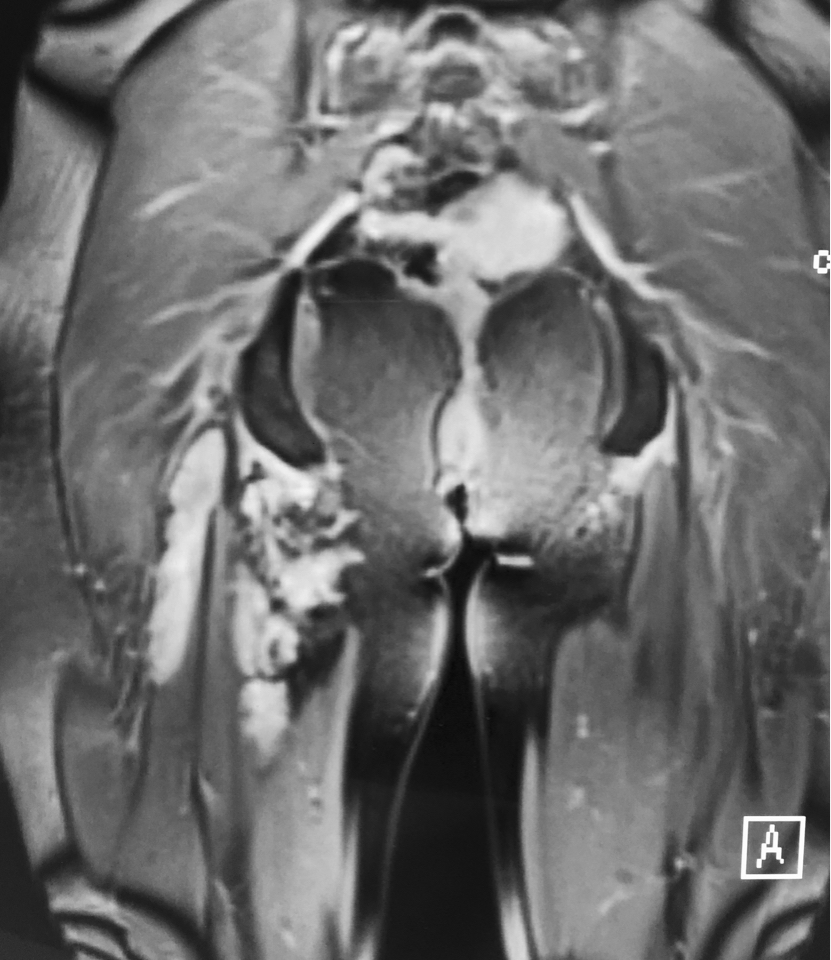

静脉畸形微创经皮硬化治疗